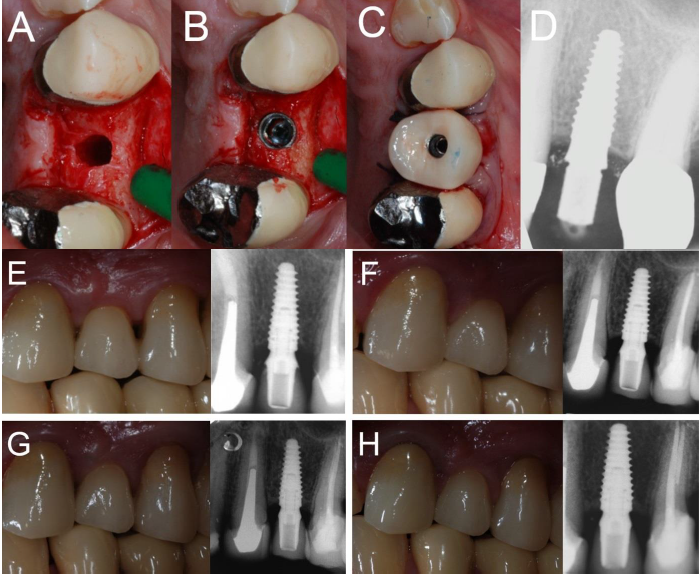

Overall, five patients could not attend the 4-year control visit and were therefore classified as drop-outs, despite the fact that the implants were still in operation. However, 4 years after insertion, only one implant was lost, in the posterior maxilla (second premolar, healed site) of a smoking woman, 48 years old at the time of surgery. The failed implant was 3.5 mm in diameter and 10.0 mm in length and was installed in bone type III. This implant failed during the first healing period, exactly two months after the insertion and immediate functional loading, as it lost stability, in the absence of infection. All the other implants were stable; therefore, the overall 4-year implant survival rate was 97.6% (patient-based, with 40/41 fixture in the survival category) and 98.1% (implant-based, with 51/52 implants in the survival category), respectively (Figures 1-4).

Figure 2. Immediate loading of a first maxillary premolar (#24) placed in a healed ridge: (A) The implant site is prepared; (B) the implant is placed at the bone crest level; (C) the provisional restoration is delivered immediately after implant placement; (D) peri-apical radiograph taken immediately after implant placement; (E) delivery of the final ceramic crown; (F) 1-year clinical and radiographic control; (G) 2-year clinical and radiographic control; (H) 4-year clinical and radiographic control.